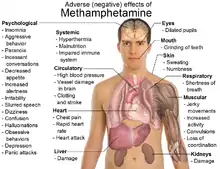

Den molekylære opbygning gør, at stoffet nemt passerer blod-hjerne-barrieren. Til forskel fra adrenalin forårsager metamfetamin ingen pludselig blodtryksstigning, men har en mildere, mere varig virkning, ofte mere end tolv timer. Konsumenten føler sig pludselig lysvågen, energien stiger, sanserne skærpes til det yderste, eufori indtræffer, og selvtilliden stiger. Fordi den intracellulære energiomsætning påvirkes, stresses nervecellerne ved høje doser. Det er som med en radio, der ikke slås af. Nervecellerne brænder ud og dør. Savner konsumenten kunstig stimulans, når virkningen aftager, er hormonlagrene tømt. Det kan tage flere uger at fylde dem igen. I mellemtiden er færre neurotransmittere i brug, og almindelige følger er nedtrykthed, slaphed og kognitive forstyrrelser.[1] Metamfetamin i ren form har færre bivirkninger end crystal meth-produkter, der ofte fremstilles af amatører i ulovlige laboratorier, ofte ispædet giftige stoffer som benzin, frostvæske eller batterisyre.[2]

Der er en lang række bivirkninger ved indtagelse af stoffet:

- Ændret søvnmønster

- Spændinger i kæberne

- Tab af appetit

- Reduceret interesse i sex (efter nogen tid)

- Kløe

- Kvalme, opkast og diarré

- Hyperaktivitet

- Åndenød

- Humørsvingninger og irritabilitet

- Nervøsitet og angst

- Aggressivitet

- Panik og paranoia

- Ufrivillige bevægelser og tics

- Falsk følelse af at være uovervindelig

- Depression og selvmordstanker

Langsigtede bivirkninger ved jævnlig brug

- Dødelige nyre- og lungesygdomme

- Mulighed for hjerneskader

- Permanente psykiske problemer

- Reduceret immunforsvar

- Leverskader

- Hjerteanfald

- Kraftig kløe

- Mundtørhed